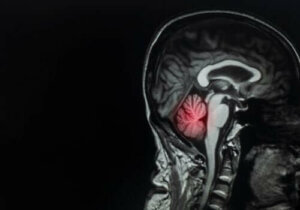

النقيلة الدماغية هي أكثر أنواع الأورام الدماغية شيوعًا، فهي تمثل 90% من حالات الأورام الدماغية، وهي من الحالات المعقدة جدًا بالنسبة للأطباء.

تشير التقديرات إلى أن بين 10% و40% من مرضى السرطان يعانون من النقيلة الدماغية. شيوع الحالة في تزايد بسبب متوسط النجاة العالي للمرض بفضل العلاجات المتطورة.

للأورام قدرة على التنقل إلى المخ وعلى اختراق الحاجز بين المخ والدم، والذي يعمل على تغطية وحماية الدماغ.